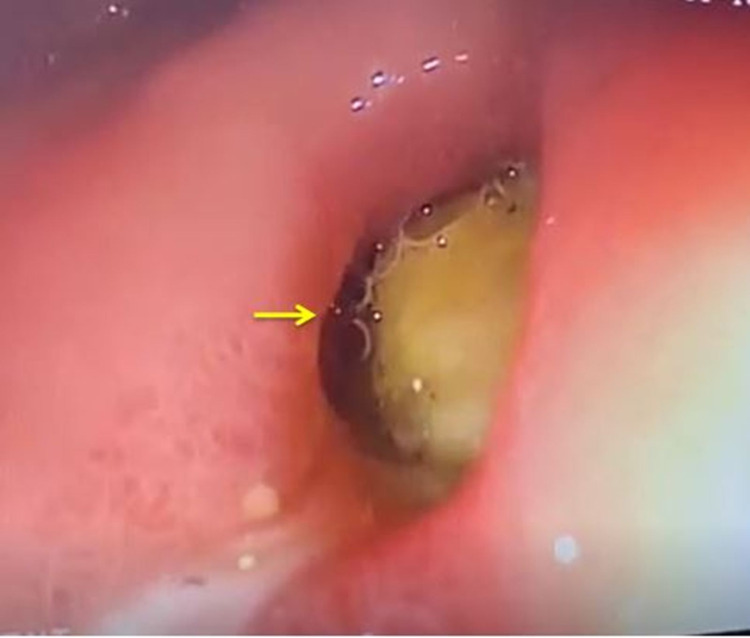

Upper gastrointestinal endoscopy showed a bulge along the lesser curvature of the stomach and fistulous opening in the first part of the duodenum (Figure 4).